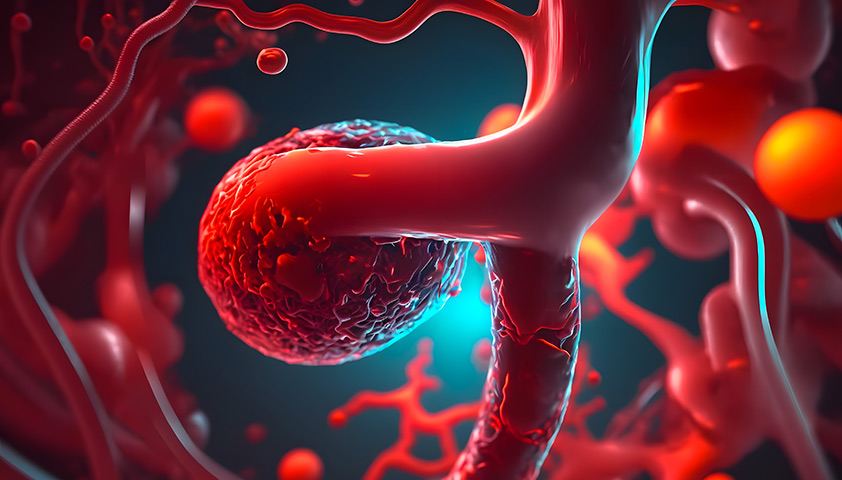

Снимки и иллюстрации микроаневризм сосудов головного мозга